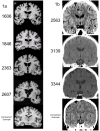

The hippocampus (HC) is necessary for learning and memory, but it also plays a role in other behaviors such as those related to stress and anxiety. In support of the latter idea, we show here that bilateral HC damage abolishes the cortisol response to psychosocial stress. We collected salivary cortisol, heart rate, and affective responses to the Trier Social Stress Test (TSST) from 7 participants with bilateral HC lesions, 12 participants with damage outside the HC, and 28 healthy normal comparison participants matched to the HC participants on age and sex. HC participants showed elevated pre-stress cortisol, but no cortisol response to the TSST. Heart rate and affective responses in the HC group were similar to those of the comparison groups. Participants with brain damage outside the HC showed stress responses that were comparable to those of the healthy comparison group. These findings support the idea that the functions of the human HC extend beyond learning and memory, and suggest that the HC is necessary for producing the cortisol response to psychosocial stress.